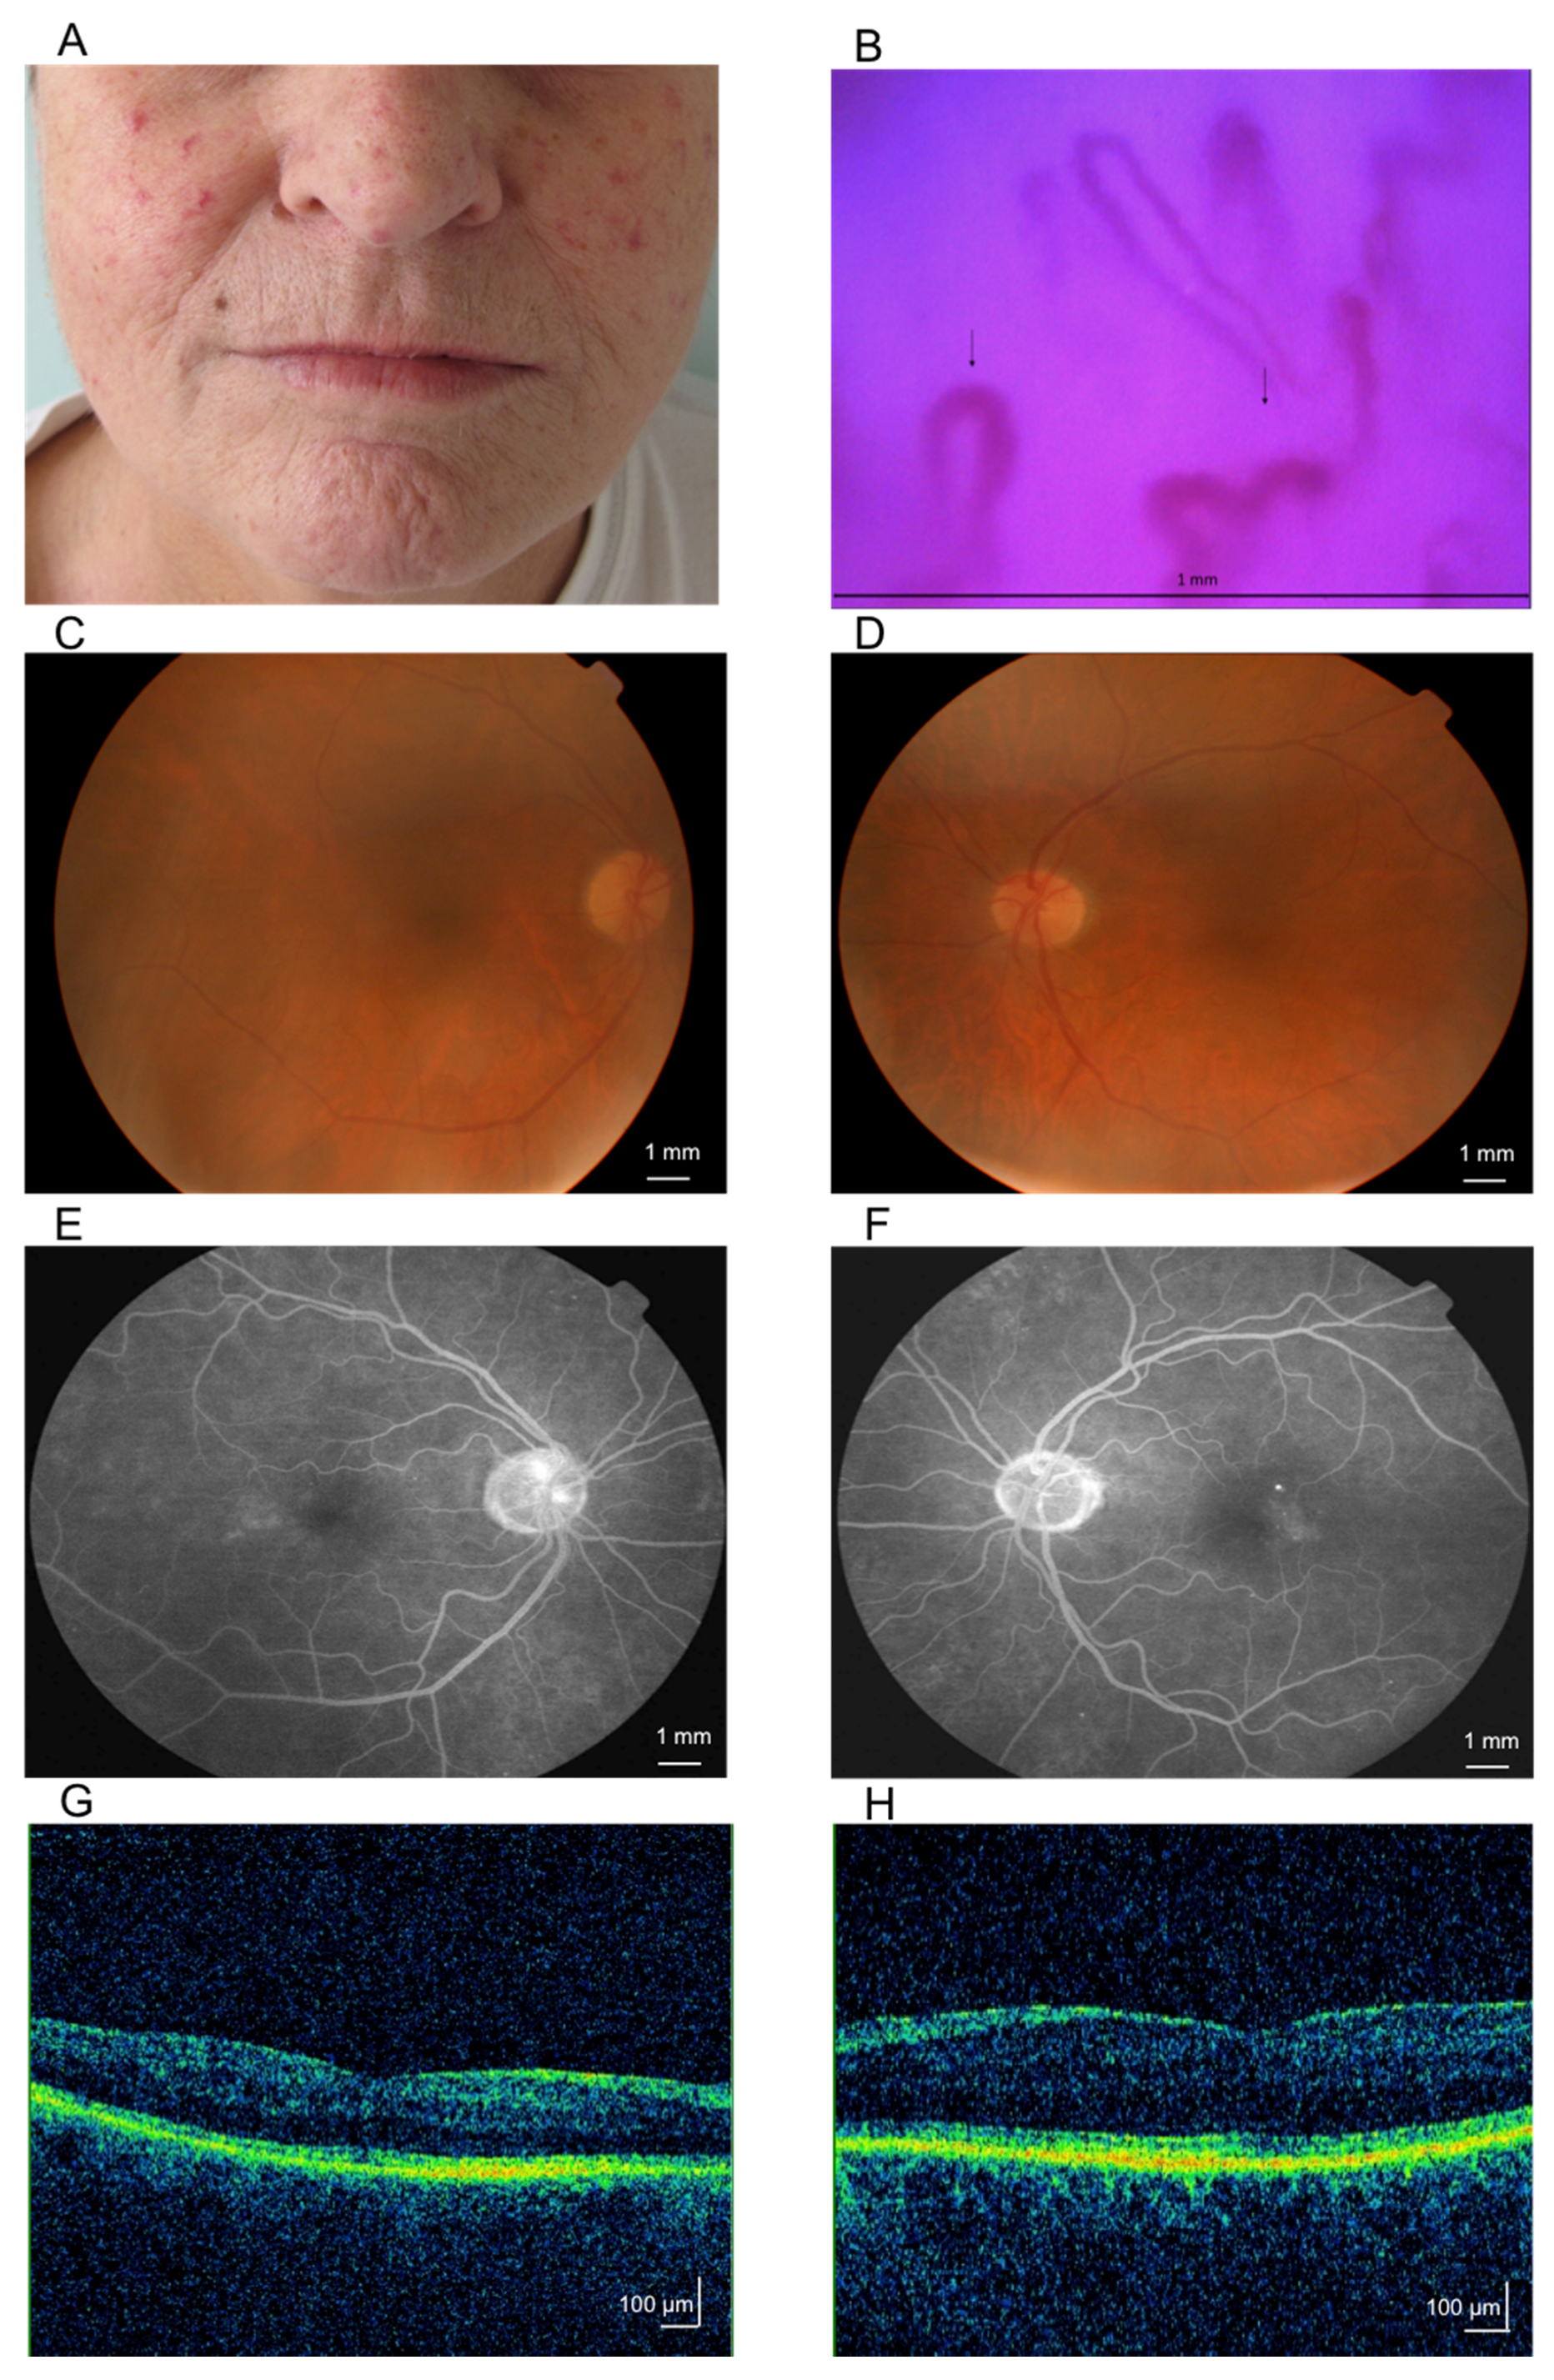

3.1. Case 1

3.2. Case 2

Fundus Fluorescein Angiography of SSc Patients